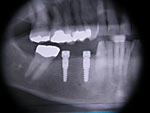

Die folgenden Patientenfälle sollen Ihnen einen Einblick in die Möglichkeiten der modernen Implantation geben.

Implantation mit externem Sinuslift: